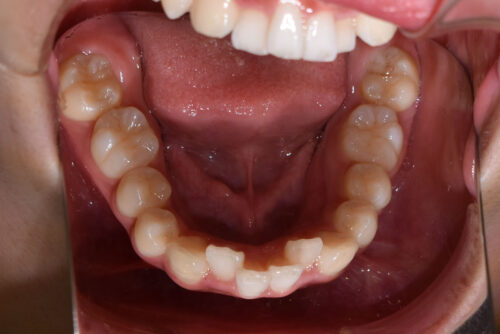

初診時年齢14歳女性

歯のがたつき(叢生)と

出っ歯

を気になさり

巣鴨 ・ 池袋よりひとつ隣駅の東京都豊島区大塚駅すぐの大塚たまみ矯正歯科へ

来院されました。

過蓋咬合: 下の歯が深く噛みこみ

また

ANGLE 2級 : 上顎前突傾向で

出っ歯を呈していました。